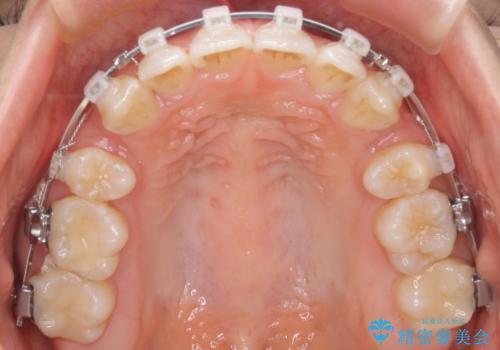

- 口元をさげたいという主訴で来院されました。4番の歯を4本抜歯し、審美装置にて治療をしました。

抜歯をしたことで口元の突出感が改善しました。約2年を予定していた矯正ですが、約1年という短い期間で終了できました。